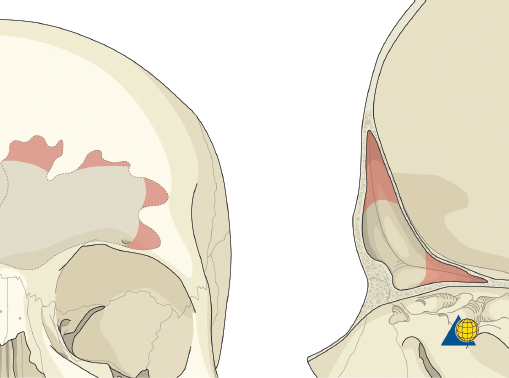

The frontal sinus contour has an intrinsic convex shape. As a perpendicular traumatic force is applied to the sinus, the convex shape is flattened. The bone is horizontally compressed until it fractures, and then it releases into a concave shape ( Fig. 63.30 ). Without significant comminution or bone displacement, fracture reduction will required enough force to pull the bone back through the compressive phase to its premorbid convex shape ( Fig. 63.31 ). While an attempt should be made to maintain the majority of fragments in situ, it may be necessary to remove a small bone fragment to release tension and allow fracture reduction. A bone hook or elevator can often be insinuated between the fragments to assist with elevation ( Fig. 63.32 ). If the bone fragments do not overlap, reduction can be accomplished by placing a 1.5- to 2-mm screw in the depressed segment, grasping the screw with a heavy hemostat, and pulling the segment anteriorly ( Fig. 63.33 ). After the bone fragments are mobilized, a 30-degree endoscope can be helpful to visualize the sinus mucosa and the nasofrontal recess. Any torn mucosa should be removed from fracture lines to avoid entrapment. The reduced fragments are then plated back in place with 1.0 to 1.3 microplates or micromesh.

Frontal Sinus Obliteration

After completion of the sinusotomy, posterior table comminution is assessed and a decision is made regarding sinus obliteration or cranialization. If the sinus is to be obliterated, meticulous debridement of all mucosa is accomplished with both cutting and diamond burs. Special attention must be paid to the periphery of the sinus where complete removal of the mucosa is most challenging ( Fig. 63.44 ). The frontal sinus infundibulum mucosa is elevated inferiorly, and a temporalis muscle plug is placed to occlude each ostia. A sharp 5-mm osteotome is then used to obtain a 5 × 5 mm outer table bone graft that can be wedged into each frontal recess to secure the muscle plug ( Fig. 63.45 ).